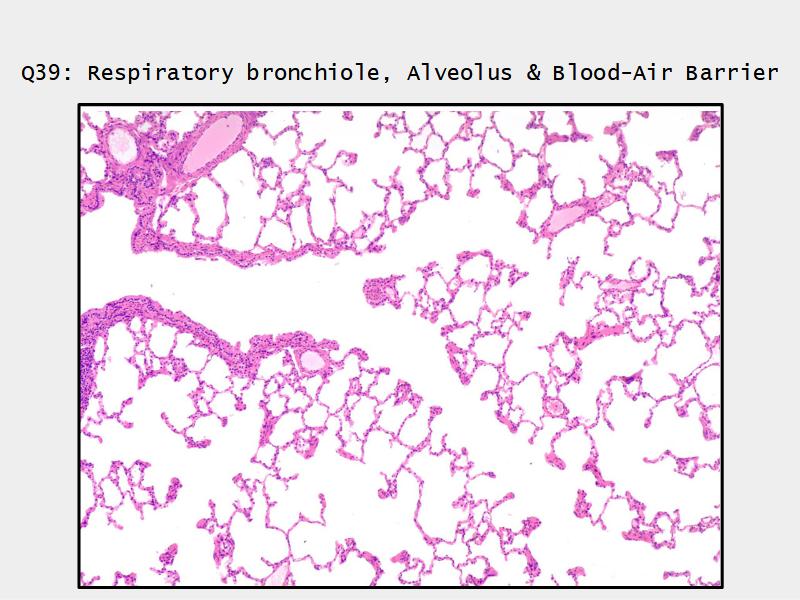

Components of the Blood-Air Barrier?

- Respiratory bronchioles

- Conducting -> Respiratory

- Simple cuboidal epithelium

- Secretory cells

- Alveoli

Lungs